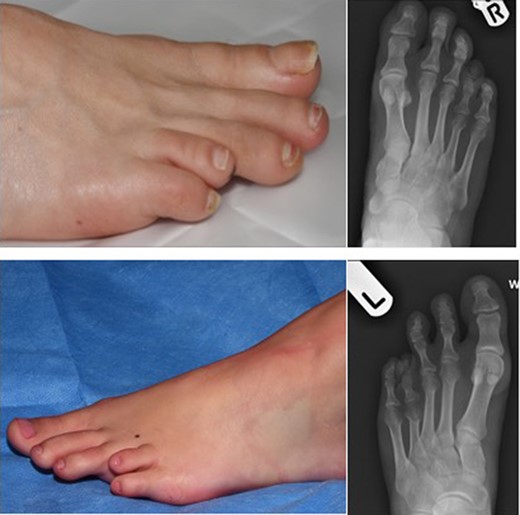

Brachymetatarsia is defined as one metatarsal ending 5 mm or more proximal to the parabolic arch of the other adjacent metatarsals [1, 2]. A shortened metatarsus can be congenital (Fig. 1) or acquired through trauma, infections, tumours or iatrogenic.

Pre-operative images on the left alongside x-rays on the right depicting congenitally short fourth toes.